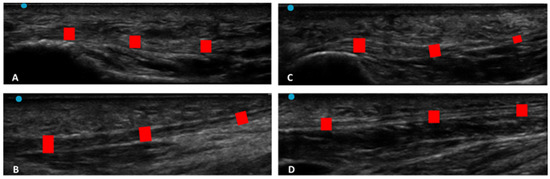

Figure 3. Ultrasound images of Crural fascia thickness: (A) group 1: Post 1 level of the leg according to Pirri et al. [33]; (B) group 1: Post 2 level of the leg according to Pirri et al. [33]; (C): group 2: Post 1 level of the leg according to Pirri et al. [33]; (D) group 2: Post 2 level of the leg according to Pirri et al. [33]. M.G.: Medial gastrocnemius muscle. L.G.: lateral gastrocnemius muscle. Red rectangles: crural fascia.

According to Sidak’s test, the comparisons between the different regions/levels of the CF and PF between group 1 and group 2 showed a statistically significant difference in the US thickness: Post 1 (group 1 vs. group 2: p = 0.03), Post 2 (group 1 vs. group 2: p = 0.03), PF level 1 (group 1 vs. group 2: p < 0.0001) and PF level 2 (group 1 vs. group 2: p < 0.0001) (Table 9 and Figure 2, Figure 3 and Figure 4).

The study’s primary aim was to investigate the differences in CF and PF thicknesses at different regions/levels in chronic Charcot diabetic foot patients compared with healthy volunteers. An analysis of our results on the CF and PF thicknesses showed that in group 1, in the posterior region of the leg at Post 1 and Post 2 levels of the CF, the latter was thicker than in group 2, showing statistical differences (Post 1: group 1 vs. group 2: p = 0.03; Post 2: group 1 vs. group 2: p = 0.03) (Table 9, Figure 2 and Figure 3).